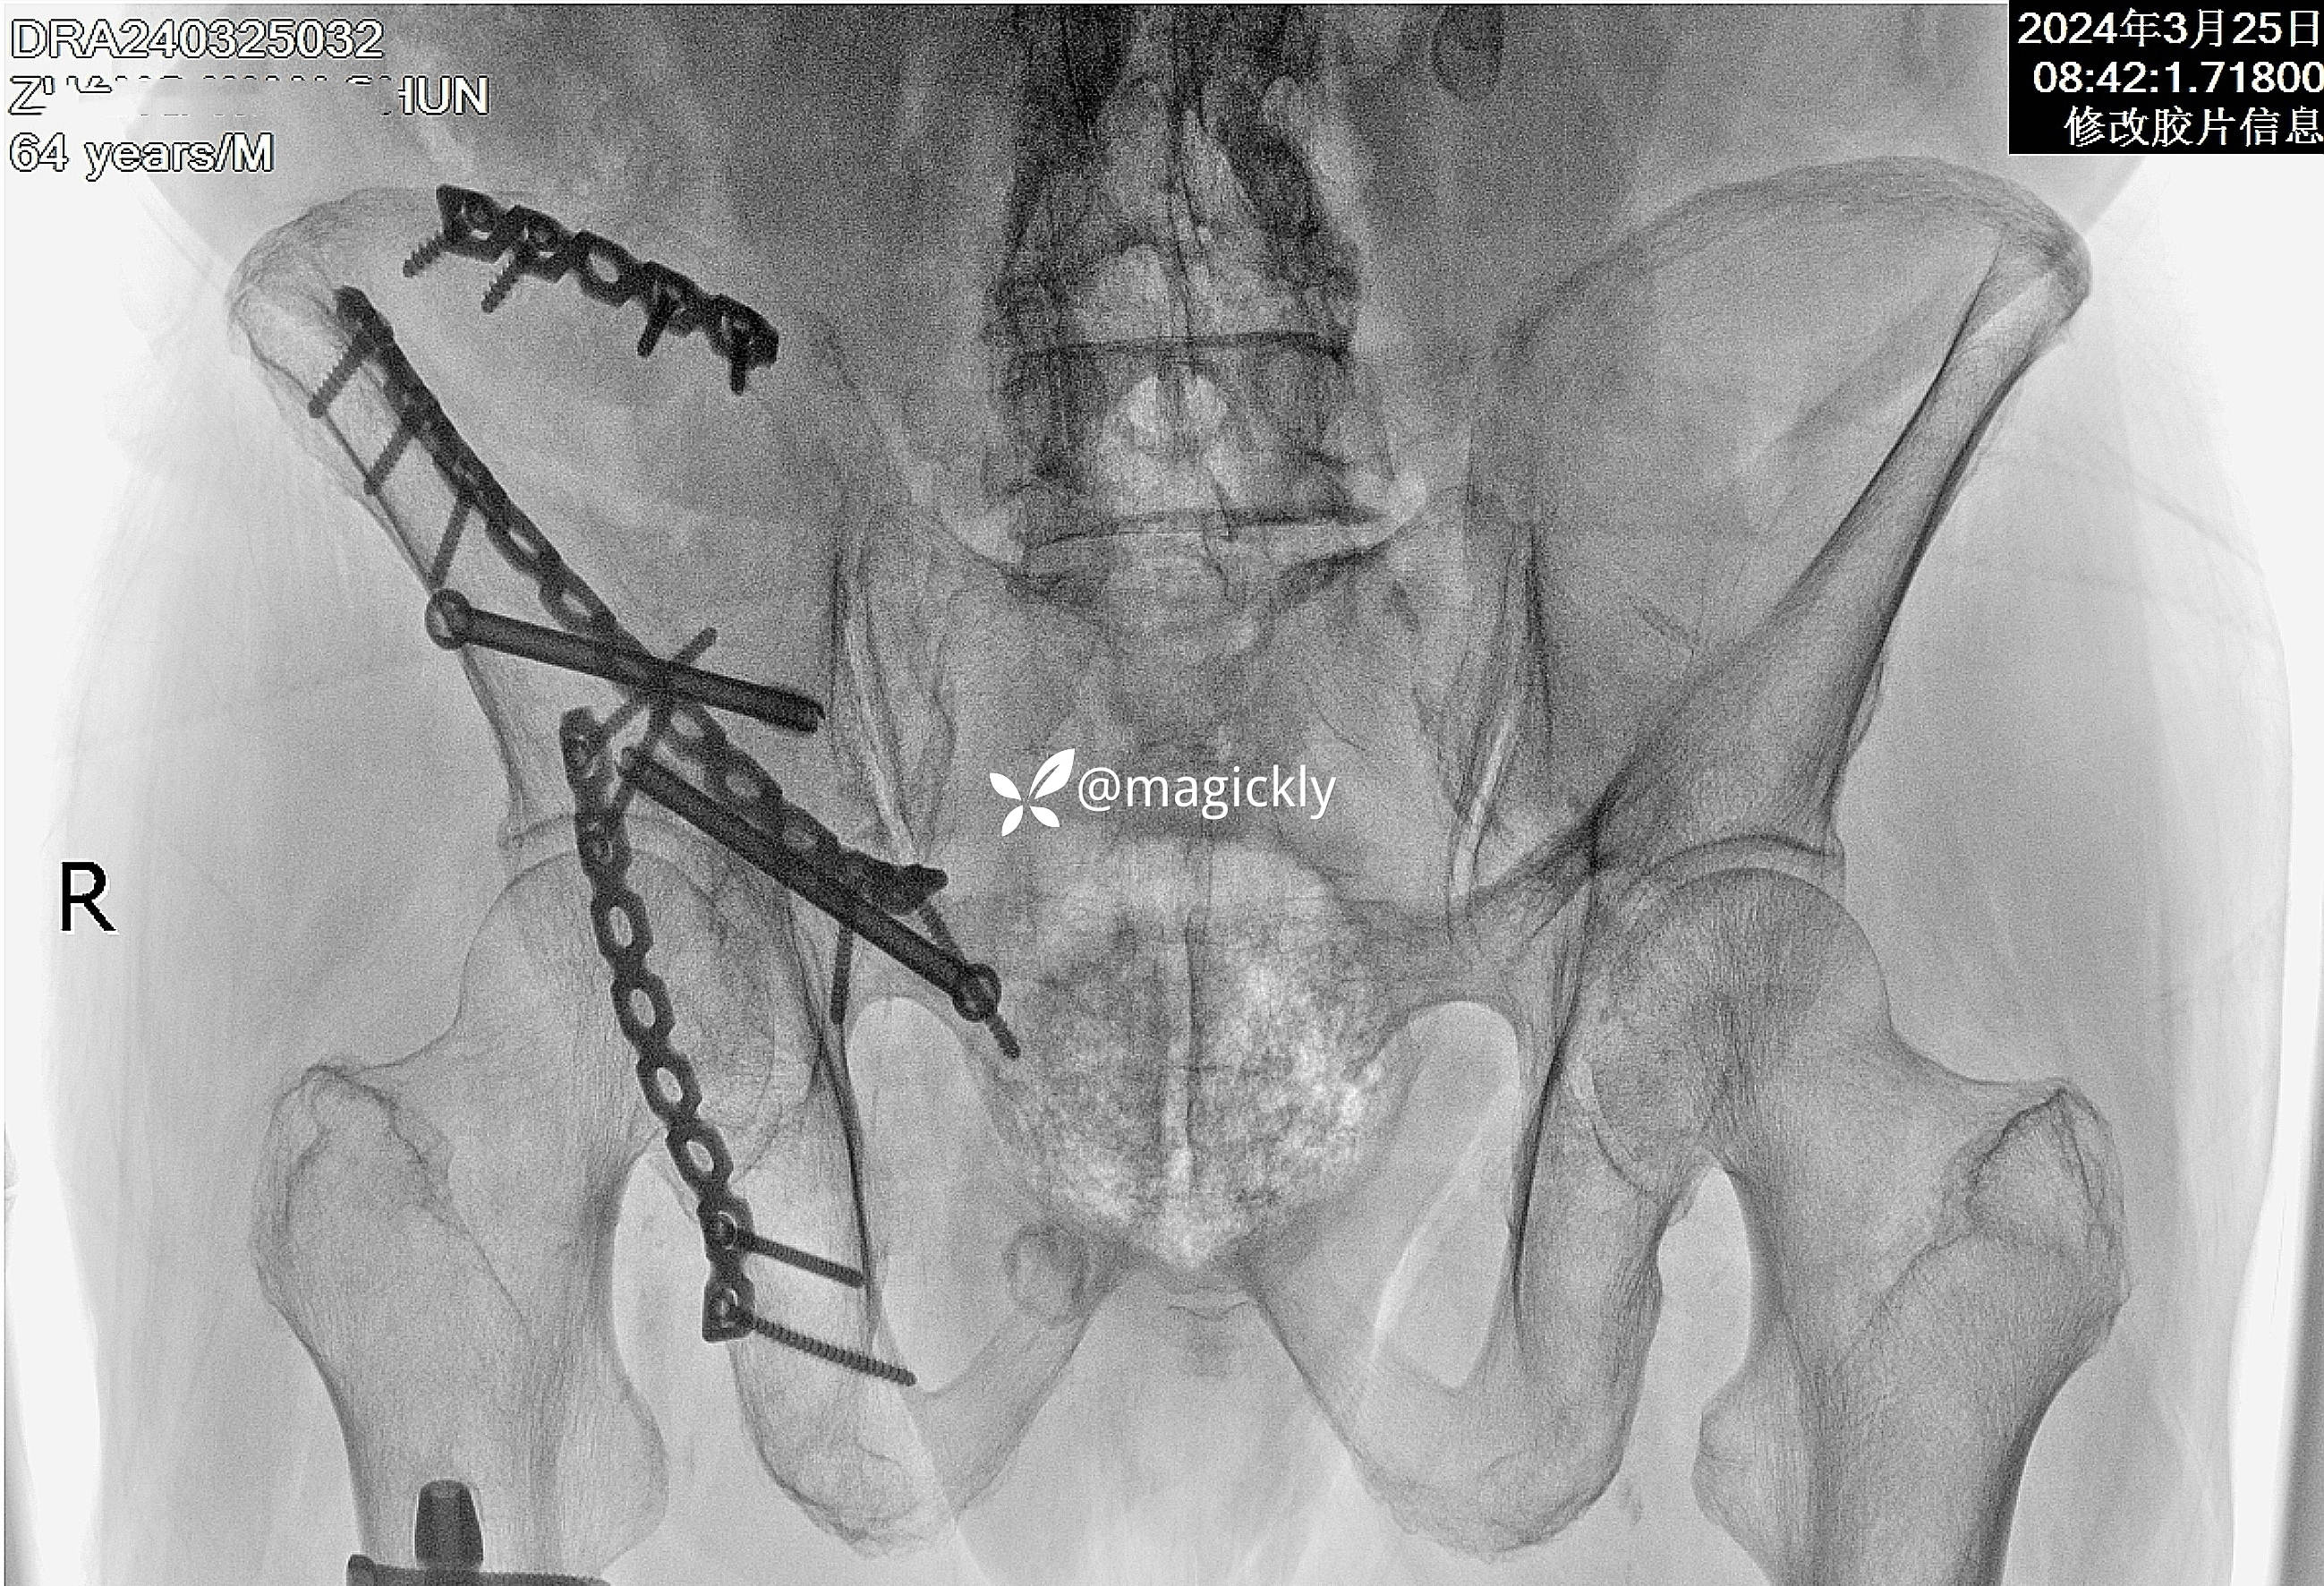

【治疗经过及结果】

img